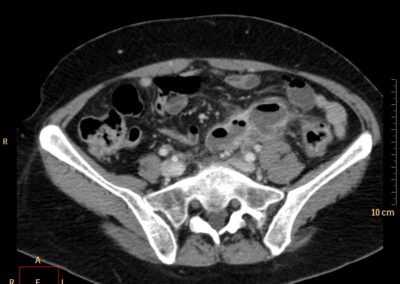

ΕΚΚΟΛΠΩΜΑΤΑ ΠΑΧΕΟΣ ΕΝΤΕΡΟΥ Posted by ΙΠΠΟΚΡΑΤΕΙΟ ΙΩΑΝΝΙΝΩΝ | Dec 16, 2020 | ΠΕΠΤΙΚΟ | 0 ΚΛΙΝΙΚΑ ΣΤΟΙΧΕΙΑ – ΙΣΤΟΡΙΚΟ υποτροπιάζοντες επαναλαμβανόμενοι πυρετοί κυρίως απογευματινές ώρες ΕΡΓΑΣΤΗΡΙΑΚΟΣ ΕΛΕΓΧΟΣ ΑΠΕΙΚΟΝΙΣΤΙΚΟΣ ΕΛΕΓΧΟΣ διακρίνονται τα αποστήματα στην ελάσσονα πύελο, καθώς και εκκολπώματα με εικόνα πάχυνσης του τοιχώματος του σιγμοειδούς ΣΥΖΗΤΗΣΗ